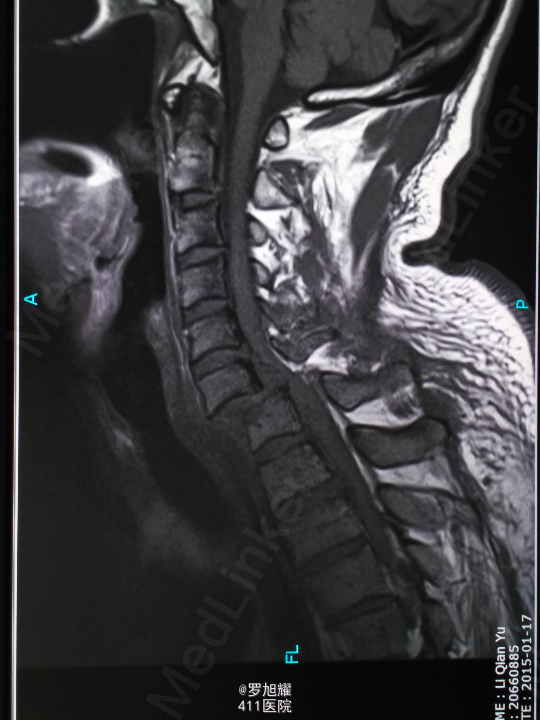

查体:双上肢前臂及以远感觉丧失,躯体自第二肋间平面以下感觉丧失。耸肩可,双侧三角肌、肱二三头肌肌力2级,腕关节屈伸、旋转及各指肌力0级。腱反射阴性,但球海绵体反射已经阳性。影像学检查示颈椎骨折脱位伴颈髓损伤。

诊断:颈6/7骨折脱位伴高位截瘫。处理:立即甲强龙冲击、脱水、保胃、营养神经治疗。首选治疗方案是颅骨牵引复位后前路融合固定,较后路稳定,出血也少,和家属谈话后开始颅骨牵引复位,4kg起步,每半小时增加1kg直至14kg,调整颈椎屈伸位,再加用手法牵引仍不能复位。改用备选方案,急诊行后路切开减压撬拨复位内固定,术后瘫痪症状部分改善。随访3月双上肢前臂及手部感觉恢复,仅双手掌尺侧及小指感觉障碍,双侧三角肌、肱二三头肌肌力4-5级,腕关节屈伸、旋转肌力左侧3级,右侧3-4级,但各指肌力仍0级。